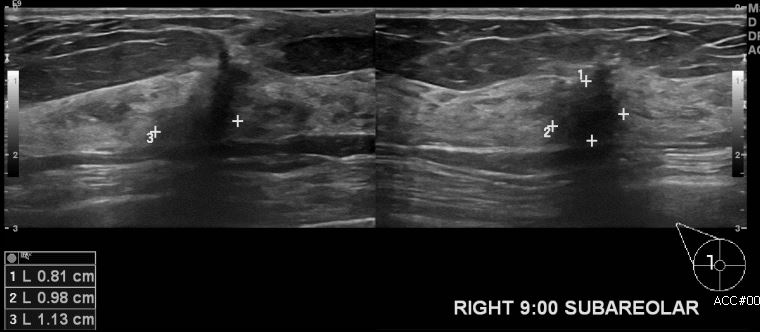

상기환자 우측 유방에 만져지는 멍울로 내원하신 50대 여성 분으로 유방 초음파

시행 후 우측 9시 방향 유두 밑 부분 조직검사 시행하여 우측 침윤성 유관암 진단되었습니다.